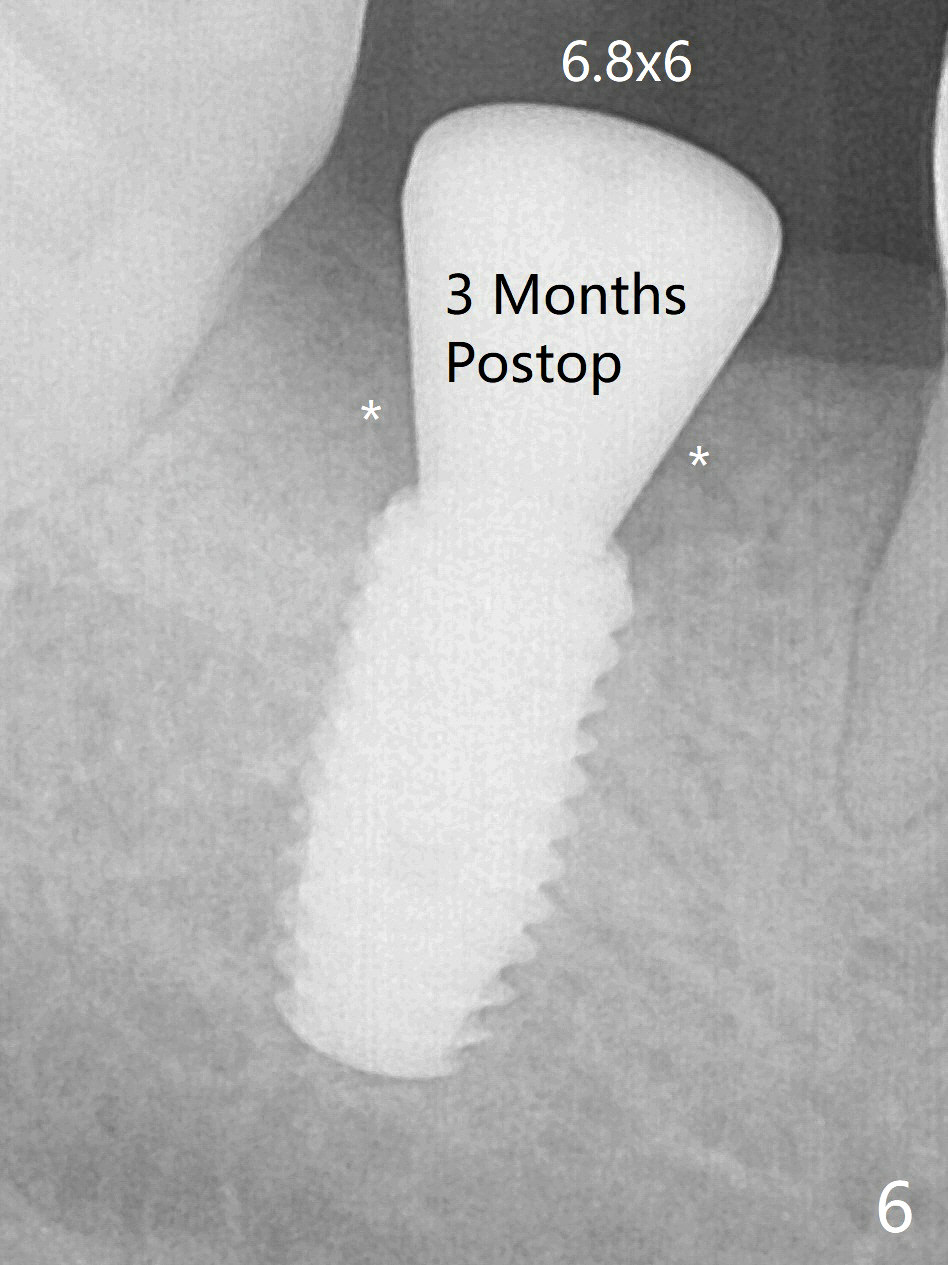

With 9 mm offset, the cylinder portion of the 2.2x8.5 mm drill does not engage to the metal sleeve of the guide at #28 after pointed drill (Fig.1). This issue could be solved with 12 mm offset, although it has no ill effect in this case. Fig.2 shows the site of #28 immediately before bone expansion and after use of 2.2x11.5 mm drill and small-scaled ridge split (^). The bone is so hard that the bone expansion is minimal (Fig.5) with autogenous bone graft and implant placement (Fig.4). There is the bone buccal to the implant clinically. A 5x10 mm implant is placed at #31 in the same appointment (Fig.3). Because of inability to masticate on the left (#18 root fracture with infection), the patient wants to restore #28 and 31 implants 3 months postop (Fig.6,7). The implant at #28 is removed while the healing abutment is being un-torqued without noting bone loss mesially (Fig.7 * (next similar case)). Bone graft is placed (Fig.8 (*),9). Pay attention radiolucency next the apex of the neighboring tooth (Fig.9 ?) before re-placement of an implant. The patient is upset, since he cannot eat. Two weeks later, a 6.5x4(4) mm cemented abutment is placed with 25 Ncm at #31 with a provisional for progressive loading for 2 weeks. Impression is taken. Two weeks later, a permanent crown is cemented without removing the underlying abutment. Two days later, the crown/abutment dislodges; a 6.8x6 mm healing abutment is placed. Eight days, it is difficult to reseat the existing crown and abutment. The mesiodistal edentulous space is limited as well. A 5.2x4(4) mm cemented abutment is able to be seated and torqued (30 Ncm) smoothly; in fact the clearance from the crestal bone (Fig.10 *) is not ample. If the abutment screw becomes loose in function, a profile drill should be used or a 4.5 mm in diameter abutment be placed. The abutment seems to remain in place immediate post cementation (Fig.11). Implant failure is probably due to no socket preservation (buccal plate atrophy) and too early restoration.